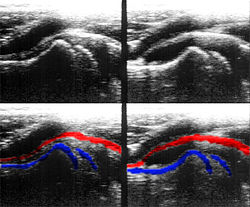

Eine weitere häufig eingesetzte Darstellungsform ist der M- oder TM-Mode (englisch für (time) motion). Dabei wird ein Strahl bei einer hohen Impulswiederholungsfrequenz (1 – 5 kHz) eingesetzt. Die Amplitude des Signals wird auf der vertikalen Achse dargestellt; die von den hintereinander liegenden Impulsen erzeugten Echozüge sind auf der horizontalen Achse gegeneinander verschoben. Diese Achse stellt also die Zeitachse dar.

Bewegungen des Gewebes bzw. der untersuchten Strukturen haben Unterschiede in den einzelnen Impulsechos zur Folge, es lassen sich Bewegungsabläufe von Organen eindimensional darstellen. Die M-Mode-Darstellung ist häufig mit dem B- bzw. 2D-Mode gekoppelt.

Ihre Hauptanwendung findet diese Untersuchungsmethode in der Echokardiografie, um Bewegungen einzelner Herzmuskelbereiche und der Herzklappen genauer untersuchen zu können. Die zeitliche Auflösung dieses Modus ist bestimmt durch die maximale Wiederholrate der Schallimpulse und beträgt schon bei 20 cm Tiefe über 3 kHz.

Farb-Doppler und PW-Doppler. Innerhalb der Stenose ist wegen der hohen Flussgeschwindigkeit und des resultierenden Alias-Effekts die Geschwindigkeit in Blau kodiert. -